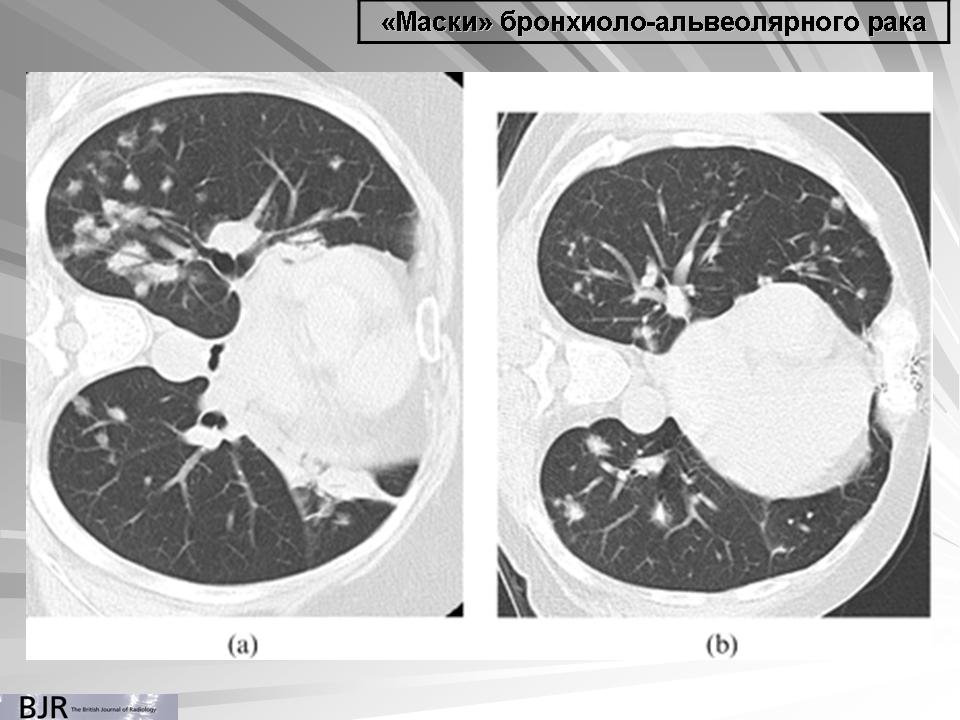

"Маски" бронхиолоальвеолярного рака.